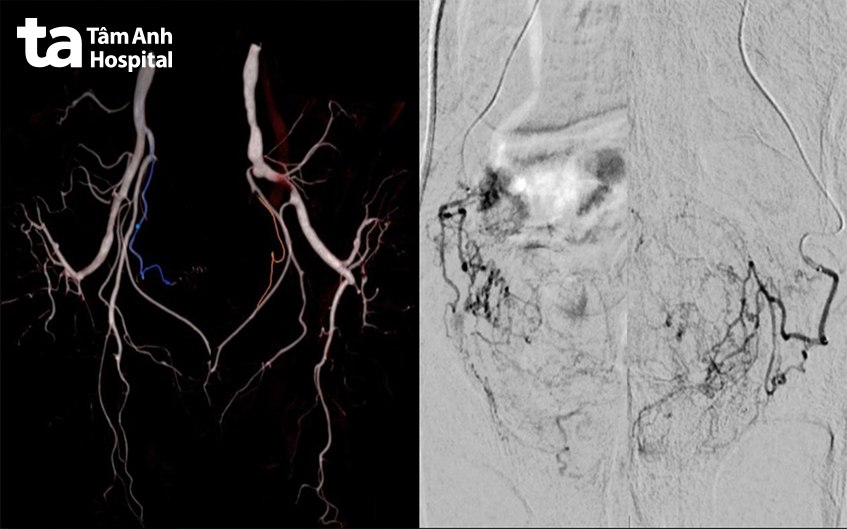

Bác sĩ Dương Đình Hoàn, Đơn vị Hình ảnh học can thiệp, Trung tâm chẩn đoán hình ảnh và Điện quang can thiệp cho biết “siêu chọn lọc” là việc chọn đúng các mạch máu nuôi tuyến tiền liệt giữa hàng trăm mạch máu vùng chậu lân cận. Bệnh viện đã ứng dụng phần mềm Embolization Guidance tích hợp trí tuệ nhân tạo (AI), để xác định và vẽ được chính xác đường đi của các mạch máu này. Từ đó, bác sĩ chọn lọc đúng mạch máu cần can thiệp, vừa rút ngắn thời gian thực hiện thủ thuật, vừa tránh được nguy cơ bỏ sót hoặc nút nhầm mạch máu nuôi các tạng lân cận. Hiện Bệnh viện Đa khoa Tâm Anh là đơn vị đầu tiên tại TP.HCM ứng dụng phần mềm này vào can thiệp nút mạch phì đại tuyến tiền liệt.

Sau khi gây tê tại chỗ ở vùng đùi, thông qua một vết đâm kim nhỏ, bác sĩ luồn hệ ống thông và dây dẫn siêu nhỏ vào lòng mạch máu. Dưới sự hướng dẫn của máy chụp mạch máu số hóa xóa nền (DSA) ống thông sẽ di chuyển và tiếp cận mạch máu tăng sinh ở tuyến tiền liệt và bơm vật liệu làm tắc các mạch máu này. Cắt nguồn máu nuôi giúp tuyến tiền liệt “bị bỏ đói”, teo nhỏ lại theo thời gian.

Quá trình thủ thuật kéo dài 90 phút, các bác sĩ đã nút thành công động mạch tuyến tiền liệt hai bên cho người bệnh. Một ngày sau can thiệp, các triệu chứng tiểu máu của ông V. đã hết và được xuất viện.